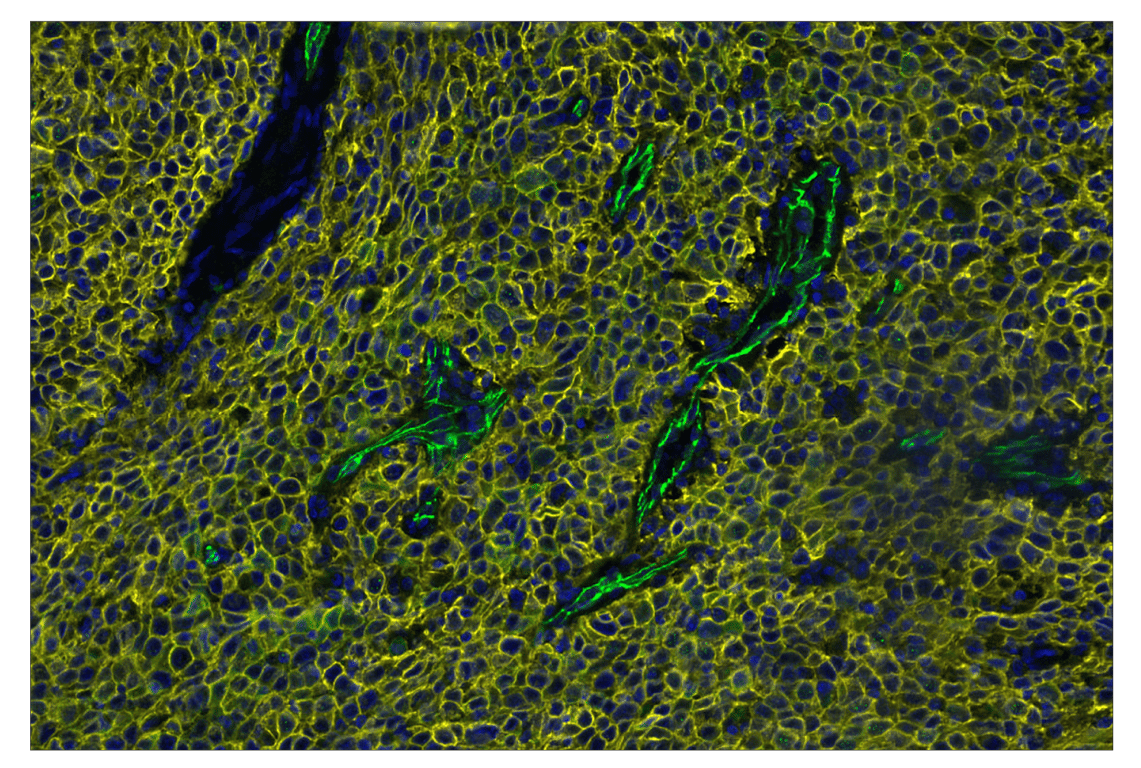

SignalStar™ multiplex immunohistochemical analysis of paraffin-embedded human squamous cell carcinoma of the cervix using VE-Cadherin (E6N7A) & CO-0149-488 SignalStar™ Oligo-Antibody Pair #53594 (green), TACSTD2/TROP2 (F4W4J) & CO-0150-594 SignalStar™ Oligo-Antibody Pair #90680 (yellow), and DAPI #4083 (blue). All fluorophores have been assigned a pseudocolor, as indicated.

Immunohistochemistry Image 3: VE-Cadherin (E6N7A) & CO-0149-647 SignalStar<sup>™</sup> Oligo-Antibody Pair